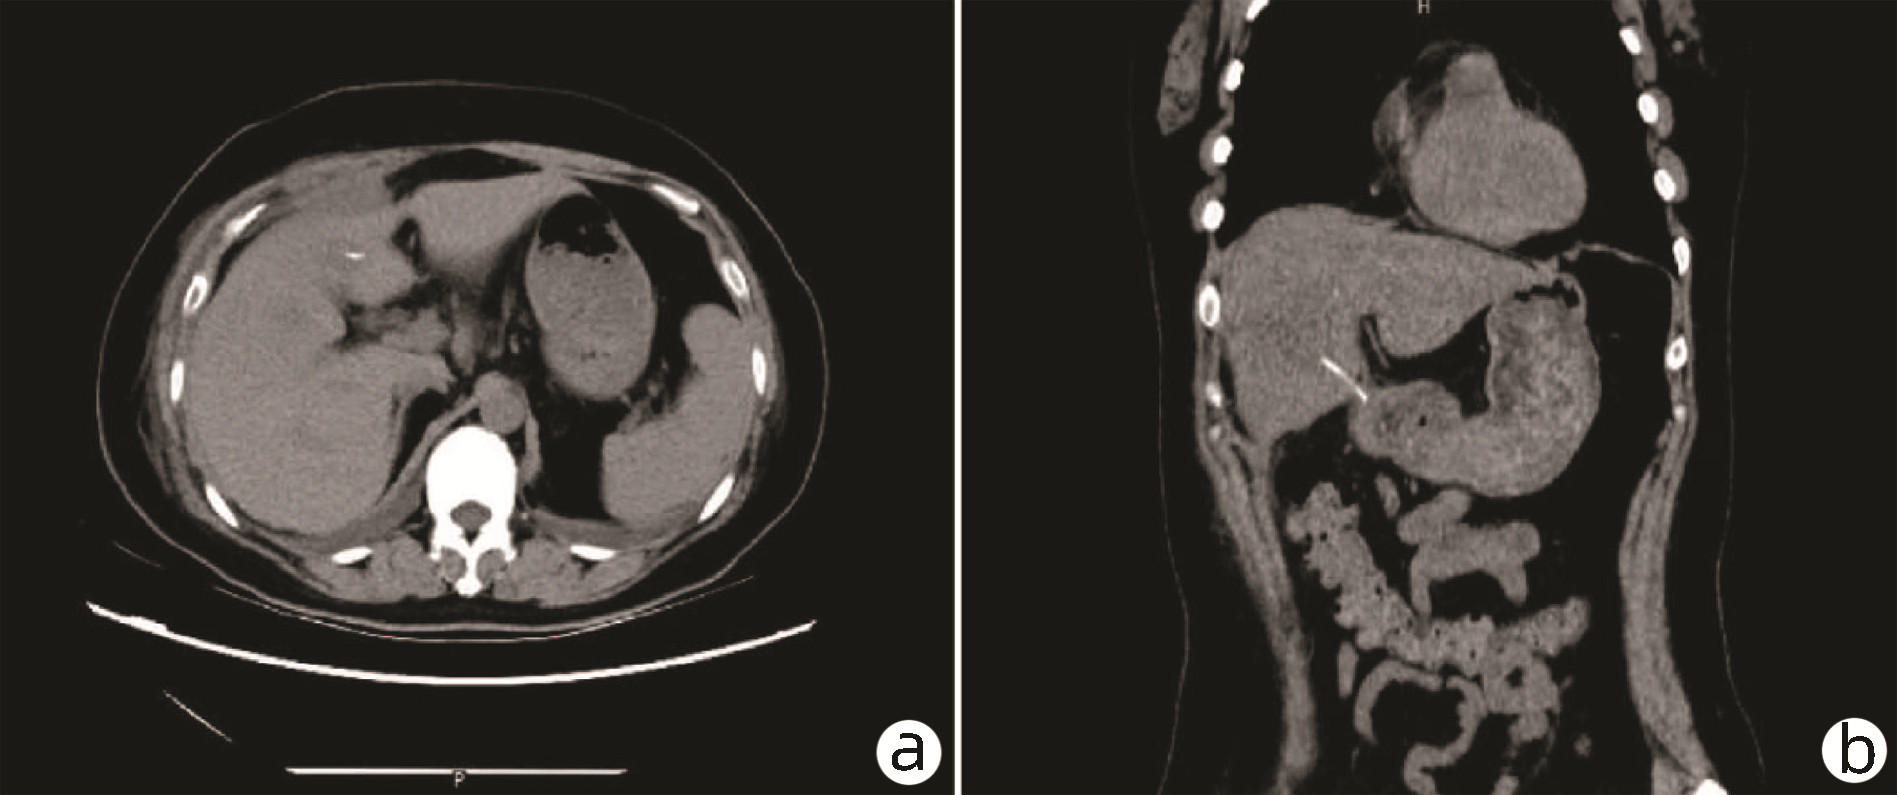

Massive hepatic hemangioma with diffuse arterioportal fistula: A case report

Bangjian ZHOU, Jun YANG, Yu YIN, Xiaoli ZHU, Caifang NI, Wansheng WANG

2023, 39(3): 640-643. DOI: 10.3969/j.issn.1001-5256.2023.03.025

Abstract(1037) HTML (228) PDF (3500KB)(109)

Abstract: